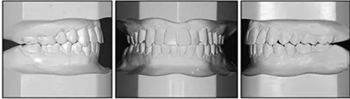

口內(nèi)相及模型:雙側(cè)磨牙、尖牙I類關(guān)系,良好的牙尖交錯(cuò)關(guān)系,覆合、覆蓋正常。

治療后50個(gè)月:治療結(jié)果基本保持穩(wěn)定,左側(cè)可見輕微復(fù)發(fā)跡象,這可能與患者的TMJ狀況有關(guān),需要進(jìn)一步治療。